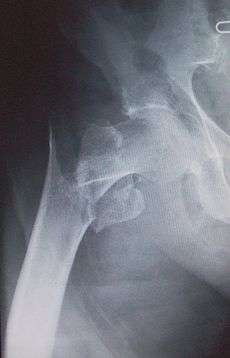

Fracture treated with cannulated screws

For low-grade fractures (Garden types 1 and 2), standard treatment is fixation of the fracture in situ with screws or a sliding screw/plate device. This treatment can also be offered for displaced fractures after the fracture has been reduced...

In elderly patients with displaced or intracapsular fractures many surgeons prefer to undertake a hemiarthroplasty, replacing the broken part of the bone with a metal implant. The advantage is that the patient can mobilize without having to wait for healing.